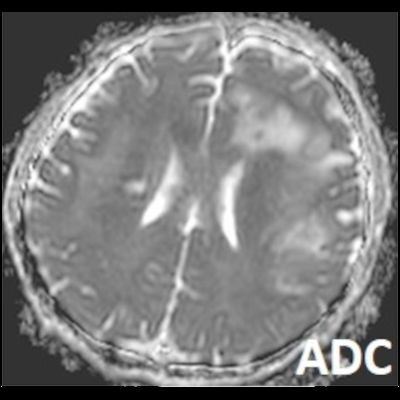

- Bilateral asimetrik subkortikal ve derin beyaz cevherde T1 ağırlıklı görüntülerde belirgin hipointens (oklar), T2A görüntülerde hiperintens (oklar), gri cevhere bakan kesimi düzgün (oklar), DAG’de hiperintens (ok) lezyonlar izlendi. Lezyonlarda T2/FLAIR uyumsuzluğu vardı (ok). Serebellar beyaz cevherde dentat nukleusu koruyan hilal işareti görüldü (ok başı). SWI sekansta sol motor kortekste hipointens kronik glioinflamatuar reaksiyon ile uyumlu sinyal değişikliği izlendi (ok başı).

- Çoğunlukla subkortikal beyaz cevherde ve U fiberlerde, asimetrik, genelde kitle etkisi yapmayan ve kontrastlanmayan demiyelinizan lezyonlar görülür. Korteks ve derin gri cevher tutulumu daha nadirdir.

- PML lezyonları, T1A görüntülerde belirgin hipointenstir. Gri cevhere bakan yüzleri keskin olup T2/FLAIR uyumsuzluğu önemli özelliğidir.